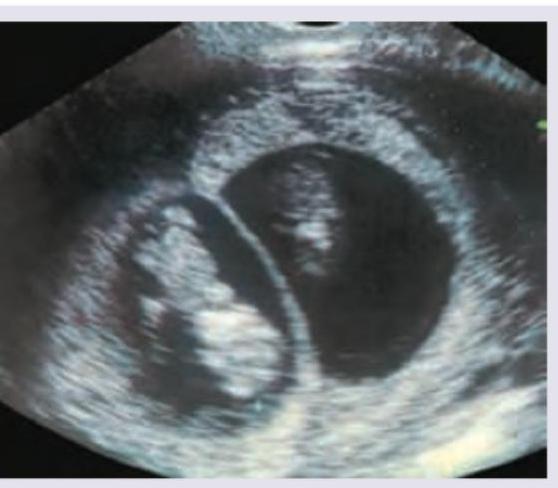

The Sonographic scan given below shows:

Explanation: ***Twins*** - The ultrasound image clearly shows two distinct **gestational sacs**, separated by a membrane, each containing a developing embryo. - This presentation is characteristic of a **twin pregnancy**, specifically dichorionic-diamniotic twins, given the visible thick membrane. *Single fetus* - A single fetus would present with only one gestational sac and one developing embryo, unlike what is seen in the image. - The presence of two separate sacs rules out a singleton pregnancy. *Snowstorm appearance* - The "snowstorm appearance" is a characteristic sonographic finding in a **hydatidiform mole**, due to hydropic villi. - This image clearly depicts recognizable fetal structures within distinct gestational sacs, which are not seen in a hydatidiform mole. *Triplets* - Triplets would involve three distinct gestational sacs or three fetuses within a shared sac (depending on chorionicity/amnionicity), but the image only shows two clear sacs. - While it's possible to miss a third sac in some views, the prominent visual here is unequivocally two.